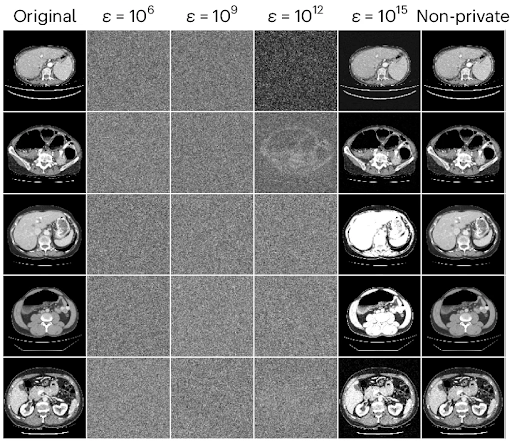

Imagine you’re building your dream home. Just about everything is ready. All that’s left to do is pick out a front door. Since the neighborhood has a low crime rate, you decide you want a door with a standard lock — nothing too fancy, but probably enough to deter 99.9% of would-be burglars. Unfortunately, the local homeowners’ association (HOA) has a rule stating that all front doors in the neighborhood must be bank vault doors. Their reasoning? Bank vault doors are the only doors that have been mathematically proven to be absolutely secure. As far as they’re concerned, any front door below that standard may as well not be there at all. You’re left with three options, none of which seems particularly appealing: Concede defeat and have a bank vault door installed. Not only is this expensive and cumbersome, but you’ll be left with a front door that bogs you down every single time you want to open or close it. At least burglars won’t be a problem! Leave your house doorless. The HOA rule imposes requirements on any front door in the neighborhood, but it doesn’t technically forbid you from not installing a door at all. That would save you a lot of time and money. The downside, of course, is that it would allow anyone to come and go as they please. On top of that, the HOA could always close the loophole, taking you back to square one. Opt out entirely. Faced with such a stark dilemma (all-in on either security or practicality), you choose not to play the game at all, selling your nearly-complete house and looking for someplace else to live. This scenario is obviously completely unrealistic. In real life, everybody strives to strike an appropriate balance between security and practicality. This balance is informed by everyone’s own circumstances and risk analysis, but it universally lands somewhere between the two extremes of bank vault door and no door at all. But what if instead of your dream home, you imagined a medical AI model that has the power to help doctors improve patient outcomes? Highly-sensitive training data points from patients are your valuables. The privacy protection measures you take are the front door you choose to install. Healthcare providers and the scientific community are the HOA. Suddenly, the scenario is much closer to reality. In this article, we’ll explore why that is. After understanding the problem, we’ll consider a simple but empirically effective solution proposed in the paper Reconciling privacy and accuracy in AI for medical imaging [1]. The authors propose a balanced alternative to the three bad choices laid out above, much like the real-life approach of a typical front door. The State of Patient Privacy in Medical AI Over the past few years, artificial intelligence has become an ever more ubiquitous part of our day-to-day lives, proving its utility across a wide range of domains. The rising use of AI models has, however, raised questions and concerns about protecting the privacy of the data used to train them. You may remember the well-known case of ChatGPT, just months after its initial release, exposing proprietary code from Samsung [2]. Some of the privacy risks associated with AI models are obvious. For example, if the training data used for a model isn’t stored securely enough, bad actors could find ways to access it directly. Others are more insidious, such as the risk of reconstruction. As the name implies, in a reconstruction attack, a bad actor attempts to reconstruct a model’s training data without needing to gain direct access to the dataset. Medical records are one of the most sensitive kinds of personal information there are. Although specific regulation varies by jurisdiction, patient data is generally subject to stringent safeguards, with hefty fines for inadequate protection. Beyond the letter of the law, unintentionally exposing such data could irreparably damage our ability to use specialized AI to empower medical professionals. As Ziller, Mueller, Stieger, et al. point out [1], fully taking advantage of medical AI requires rich datasets comprising information from actual patients. This information must be obtained with the full consent of the patient. Ethically acquiring medical data for research was challenging enough as it was before the unique challenges posed by AI came into play. But if proprietary code being exposed caused Samsung to ban the use of ChatGPT [2], what would happen if attackers managed to reconstruct MRI scans and identify the patients they belonged to? Even isolated instances of negligent protection against data reconstruction could end up being a monumental setback for medical AI as a whole. Tying this back into our front door metaphor, the HOA statute calling for bank vault doors starts to make a little bit more sense. When the cost of a single break-in could be so catastrophic for the entire neighborhood, it’s only natural to want to go to any lengths to prevent them. Differential Privacy (DP) as a Theoretical Bank Vault Door Before we discuss what an appropriate balance between privacy and practicality might look like in the context of medical AI, we have to turn our attention to the inherent tradeoff between protecting an AI model’s training data and optimizing for quality of performance. This will set the stage for us to develop a basic understanding of Differential Privacy (DP), the theoretical gold standard of privacy protection. Although academic interest in training data privacy has increased significantly over the past four years, principles on which much of the conversation is based were pointed out by researchers well before the recent LLM boom, and even before OpenAI was founded in 2015. Though it doesn’t deal with reconstruction per se, the 2013 paper Hacking smart machines with smarter ones [3] demonstrates a generalizable attack methodology capable of accurately inferring statistical properties of machine learning classifiers, noting: “Although ML algorithms are known and publicly released, training sets may not be reasonably ascertainable and, indeed, may be guarded as trade secrets. While much research has been performed about the privacy of